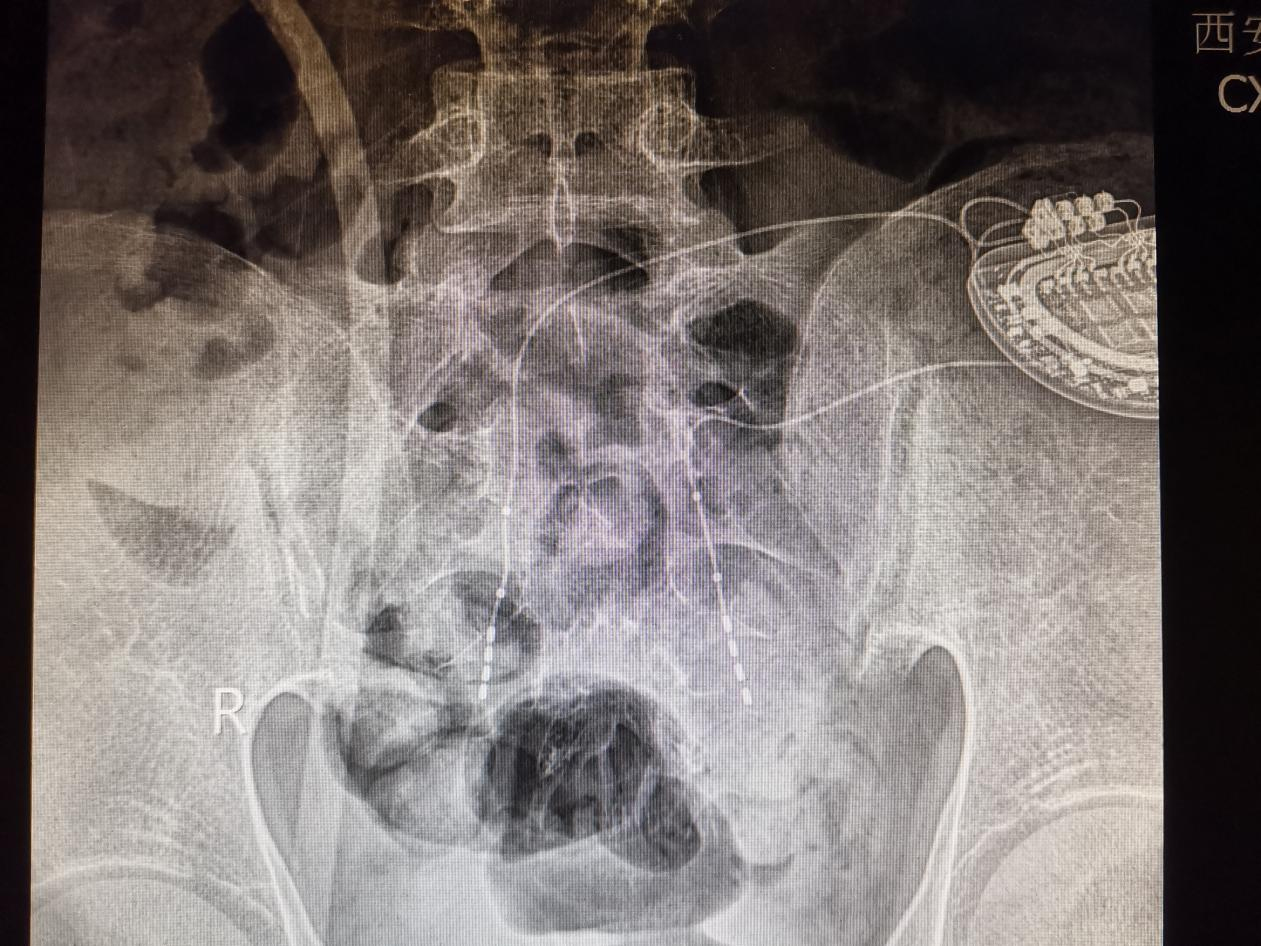

(植入可充电双接口骶神经刺激器)

(X线下刺激器位置)